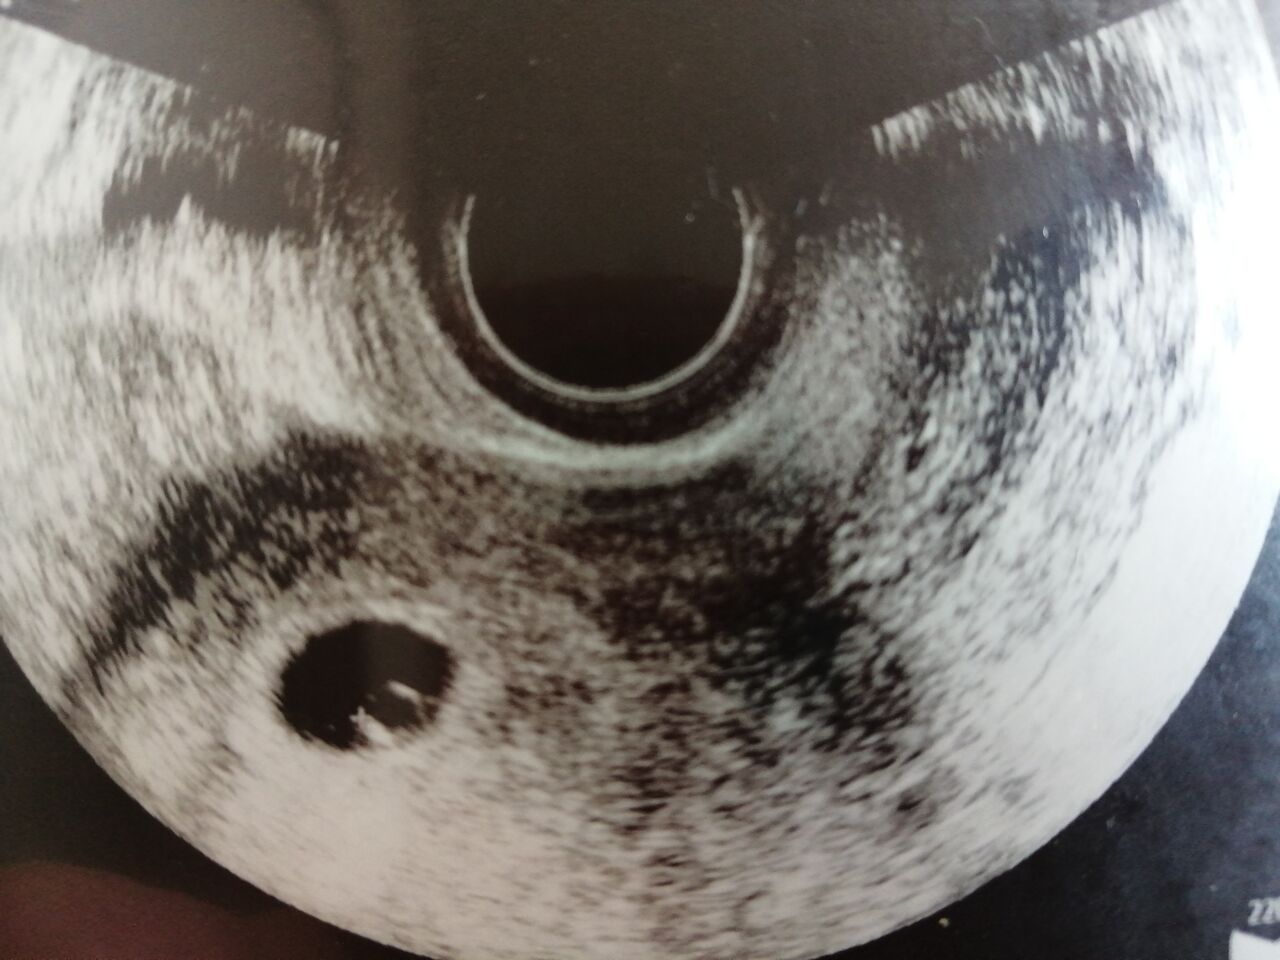

実際、移植する直前の娘がこれ。

解凍したら卵の殻を破って

元気に出てきたらしい。

やっぱ生命力があったんだろな。

3BBだった卵が5BBに

2段階も成長してました。